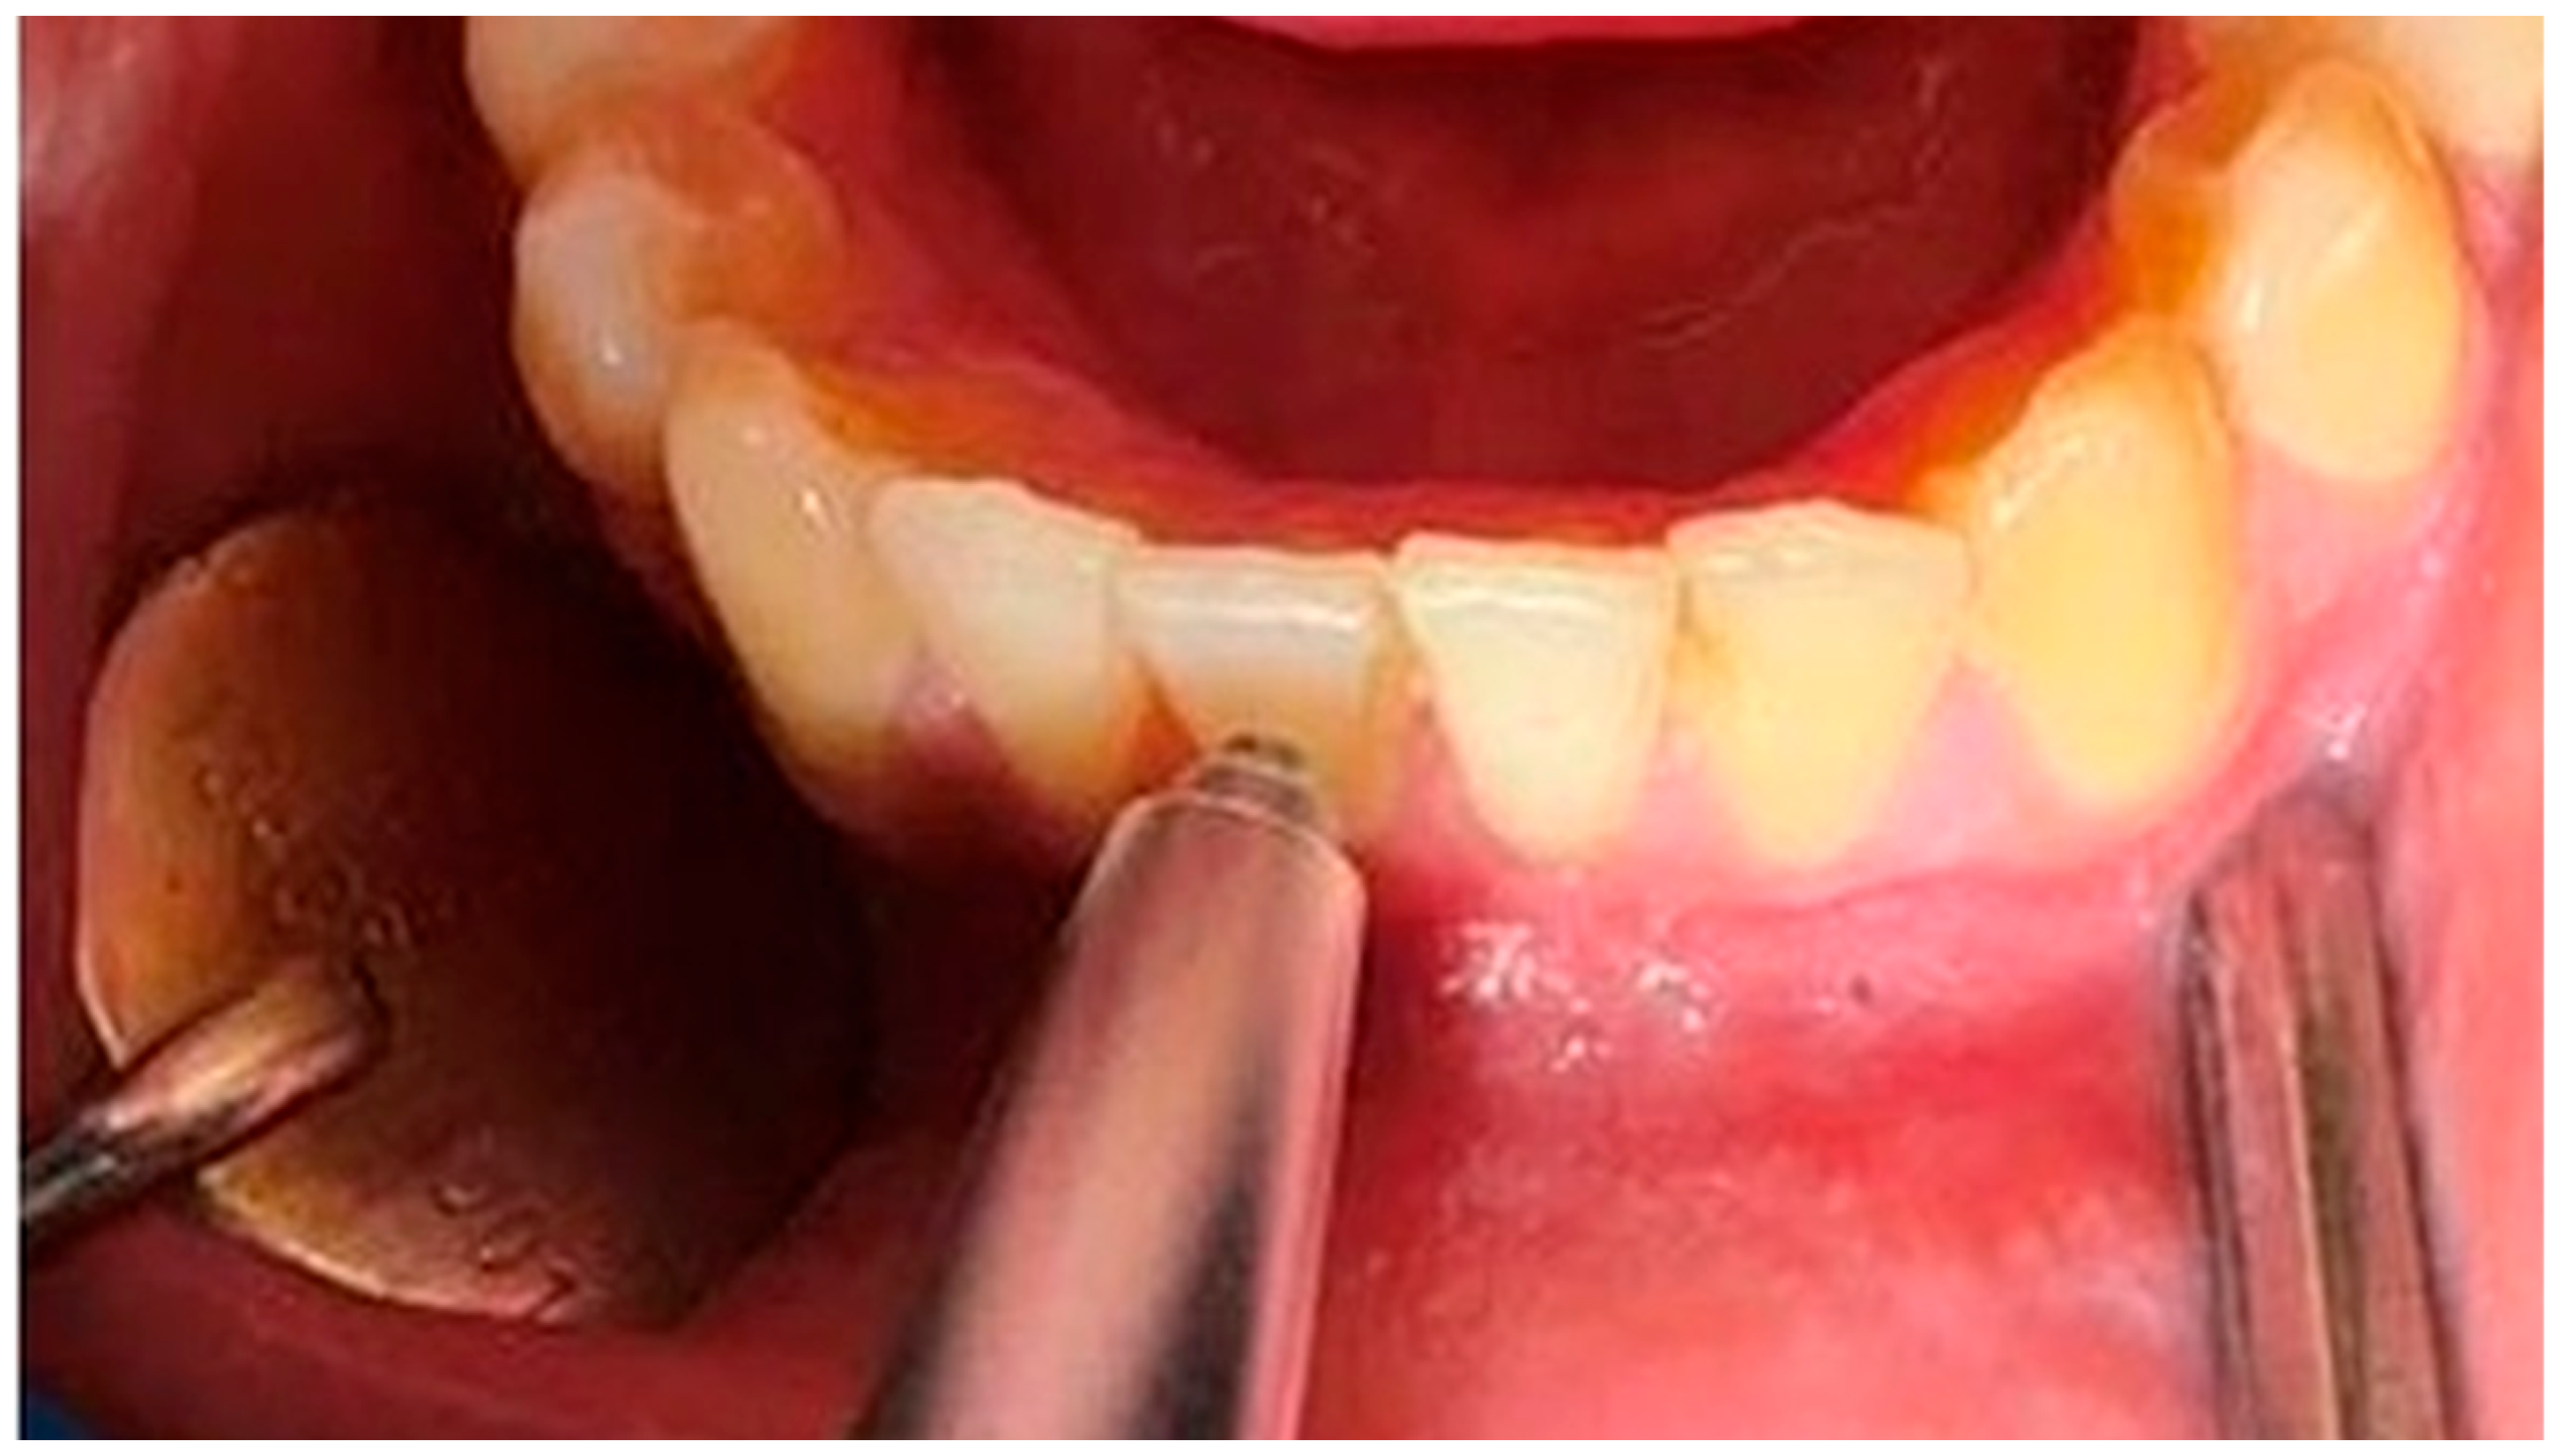

2. Materials and Methods